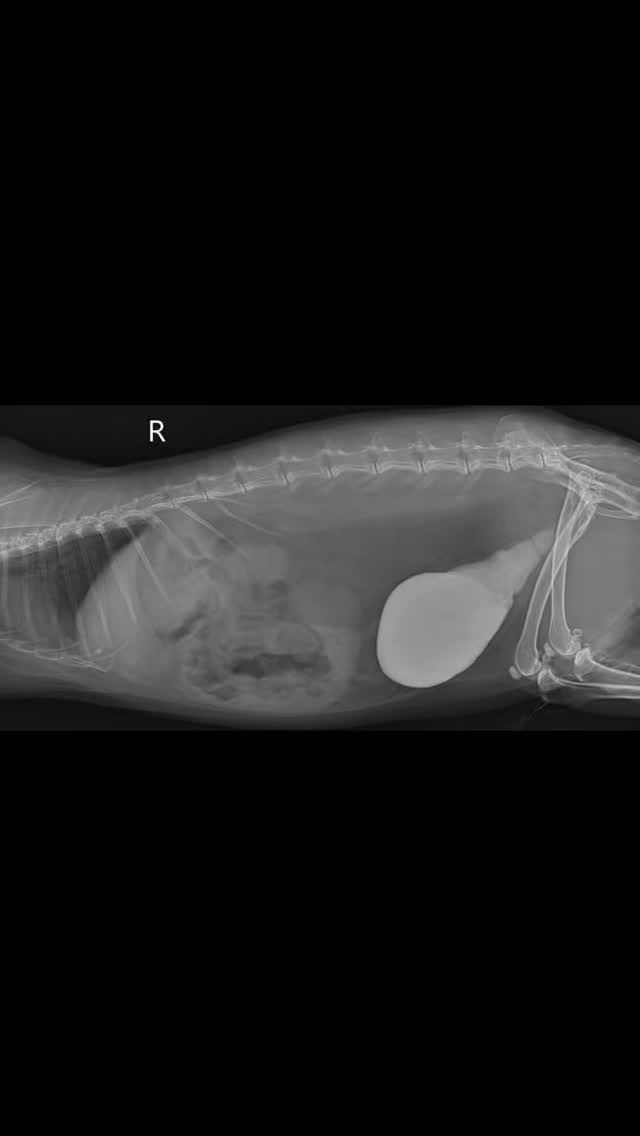

Eine fundierte Diagnostik ist uns besonders wichtig. Unser In-House-Labor ermöglicht uns die schnelle Analyse von Blut-, Urin-und Kotproben direkt vor Ort, ergänzt durch digitale Röntgentechnik und Ultraschalluntersuchungen.